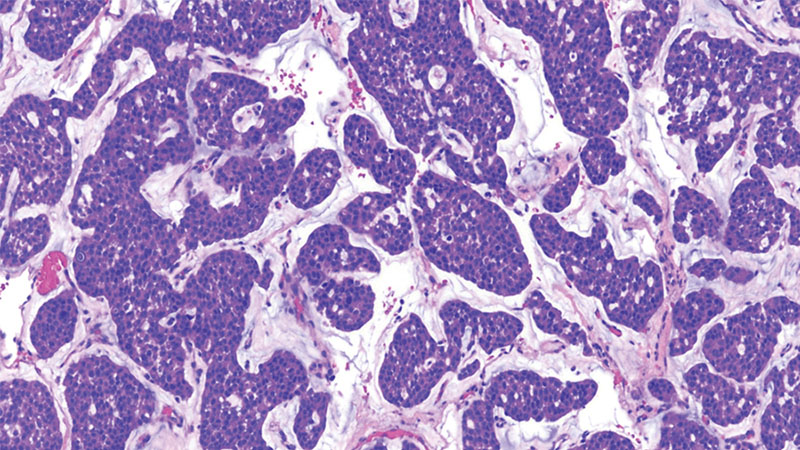

Expert Pathology Reports

At Northwestern Medicine, our renowned neuropathology team specializes in tumors of the central nervous system. We provide comprehensive evaluations for brain and spine tumors, including integrating clinical, radiologic, pathologic and molecular data to ensure the most accurate diagnoses possible. We are able to conduct these analyses even on tissue which has been resected (removed) at other institutions.